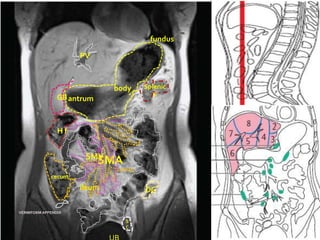

fundus

body     Splenic

GB antrum                F

SMV

SMA

cecum

ileum            DC

VERMIFORM APPENDIX